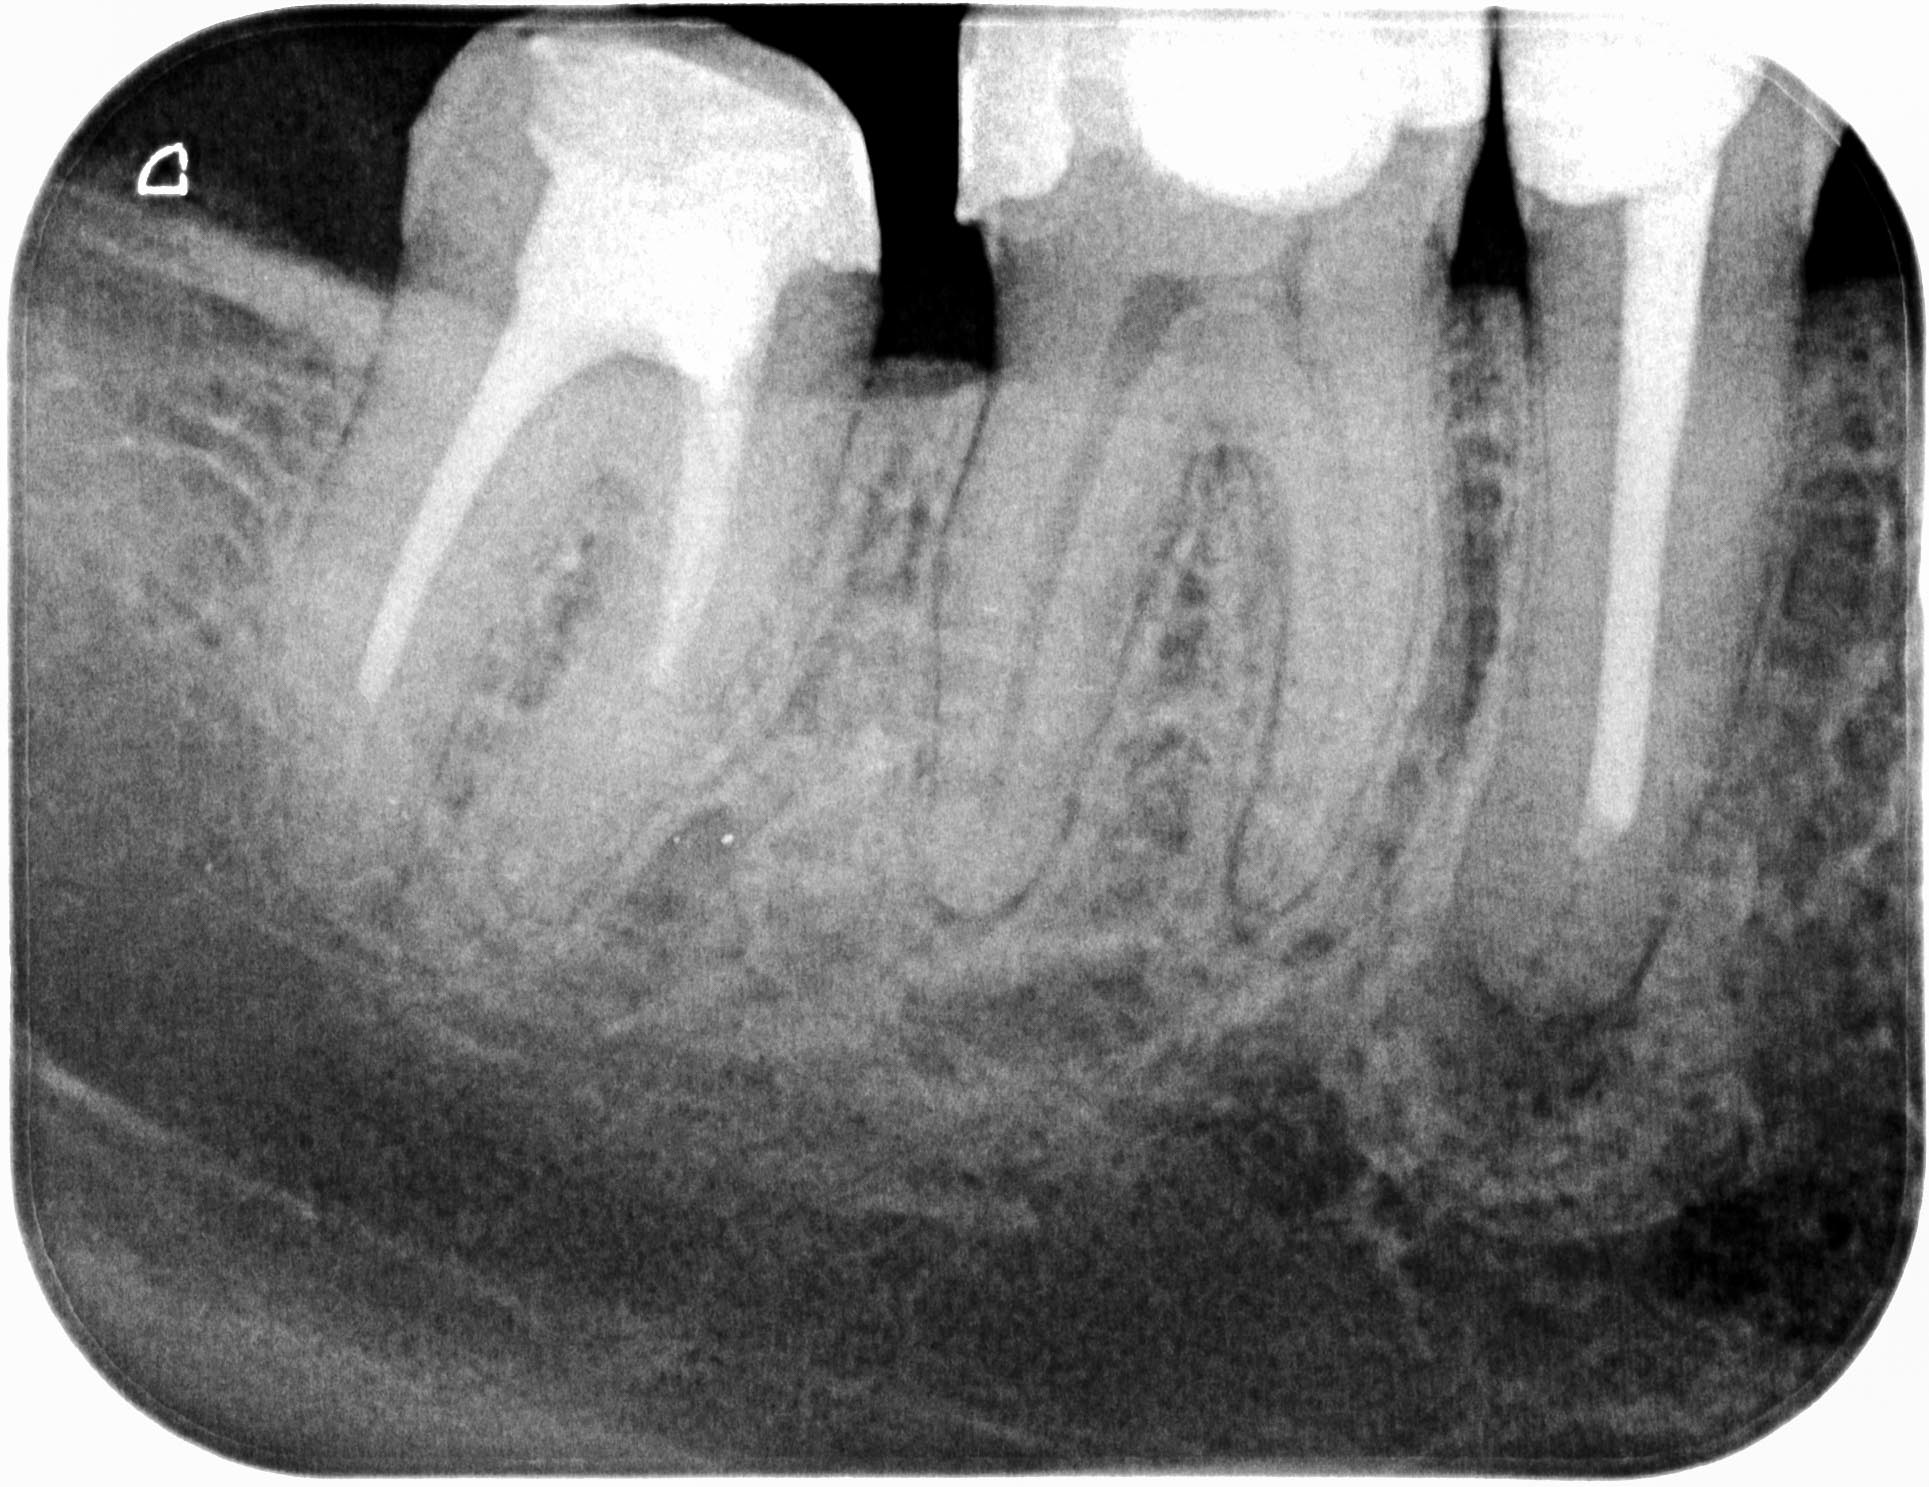

3 Haselnüsse (2)